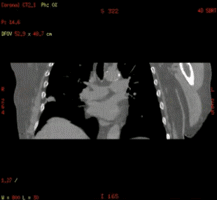

在放射治疗科,我可以进行放疗患者CT定位扫描,我可以不依靠第三方厂家,自己做四维呼吸门控扫描,我可以自动去除患者金属伪影,我的老搭档SIM兄弟可以自动勾画正常器官外轮廓,支持在四维CT图像上实时定义修改结构,可以存储为RT DICOM格式发送给TPS。

D4D可独立完成四维CT扫描,简化扫描流程效率更高